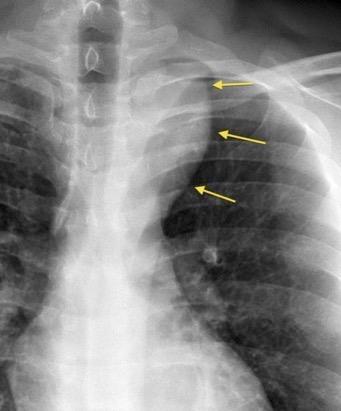

La densidad aumentada con desplazamiento lateral de la VCS es el signo más fiable

Adenopatías > 15 mm. (98 pacientes)

Ensanchamiento de la banda paratraqueal........35%

Aumento del ganglio de la ácigos.......................42%

Convexidad lateral de la VCS.................................47%

Densidad aumentada en la zona de la VCS.........83%

Müller NL. et al. Radiology 1985